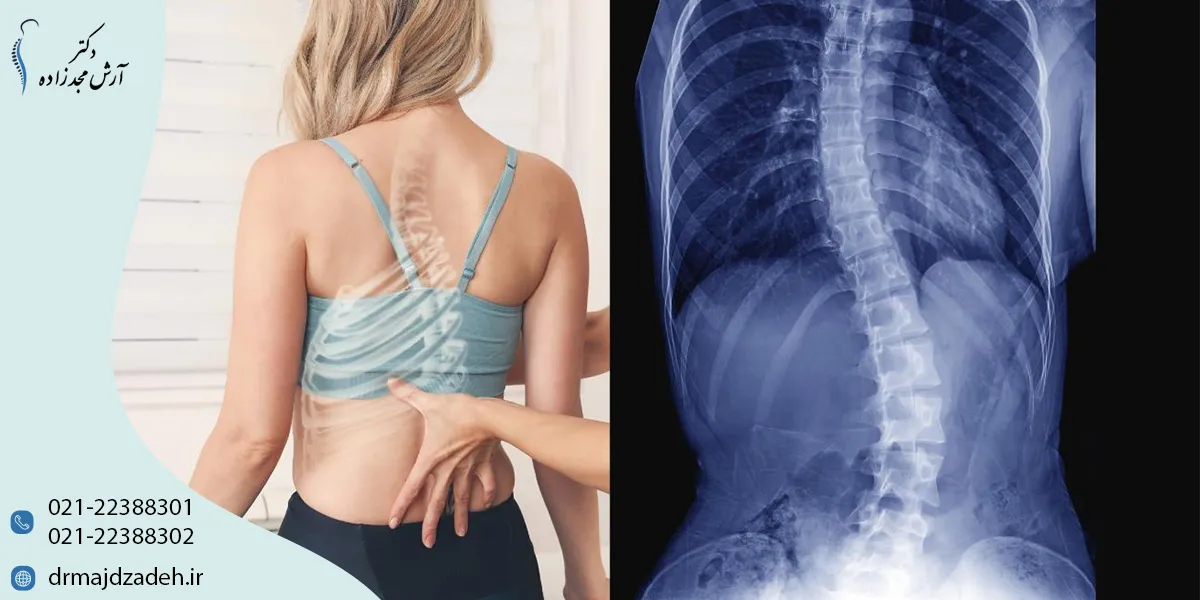

اسکولیوز چیست و چه علائمی دارد؟

اسکولیوز (Scoliosis) نوعی انحراف جانبی ستون فقرات است که باعث میشود مهرهها از خط مستقیم خارج شوند و بدن از پشت به شکل حرف S یا C دیده شود.

در حالت طبیعی، ستون فقرات انحناهای فیزیولوژیکی ملایمی دارد (در ناحیه گردن، قفسه سینه و کمر)، اما در اسکولیوز، این انحناها بهصورت غیرطبیعی و جانبی ایجاد میشوند.

طبق تحقیقات Mayo Clinic، حدود ۲ تا ۳ درصد از افراد به نوعی از اسکولیوز مبتلا هستند و در بسیاری از موارد، این وضعیت از دوران نوجوانی آغاز میشود.

علائم شایع اسکولیوز

| علامت | توضیح |

| نابرابری شانهها | یکی از شانهها بالاتر از دیگری است. |

| برجستگی یک سمت کمر | هنگام خم شدن به جلو، برآمدگی یک سمت کمر مشخص میشود. |

| چرخش لگن یا ناهماهنگی اندامها | یک سمت لگن بالاتر یا جلوتر است. |

| درد یا خستگی در کمر | ناشی از فشار عضلانی و تغییر مرکز ثقل بدن |

| مشکلات تنفسی | در موارد شدید، بهدلیل فشردگی قفسه سینه |